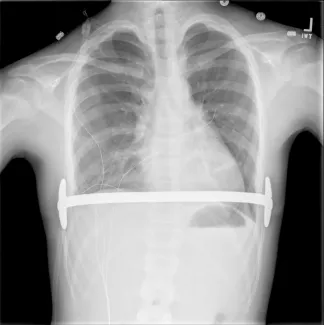

Repair with a metal pectus bar, called the Nuss Procedure, is achieved by bending a stainless bar to fit the chest wall. The bar is then inserted and secured through a small incision under each arm using the aid of a endoscope to monitor and avoid injury to the heart during insertion. The bar goes over the ribs and under the sternum, to push the sternum forward into the new position. The ends of the bar are secured to the chest wall. This procedure takes between 1–2 hours.

Preoperatively, your insurance carrier may require a CT scan to measure the Pectus Severity Index (PSI, also known as the Haller Index), which is the the ratio of the width of the chest wall to the depth at the deepest point of the deformity. This value usually must exceed 3.2 to be considered severe enough to be surgically corrected.